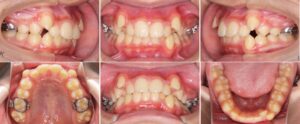

口元突出、口唇閉鎖不全(口唇がうまく閉じれない)を主訴とした大人の矯正治療についてご紹介いたします。

19才女性の症例です。

「前歯が出ていてうまく物が噛めない、見た目がコンプレックス」と相談に来られました。

詳しく調べてみると、顎の位置も不安定であったため、まず「顎の位置を安定させる装置(スプリント)」を使って、顎位の安定を図りました。

その後、矯正治療を行いました。

上下の左右4番の歯を抜歯し、マルチブラケット装置(ワイヤーの装置)や上顎に力をかける器具(パラタルバー)、アンカープレートを使って歯列と咬合の改善を図りました。

矯正治療費用:¥1,034,000

矯正治療期間:1年11ヶ月

矯正治療回数:15回

治療前

治療中

治療後